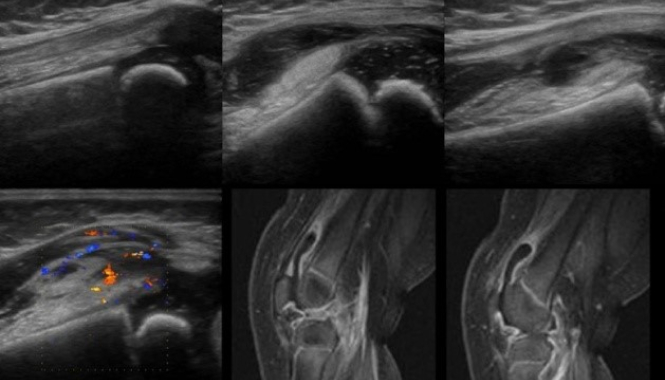

УЗИ коленных суставов назначают для оценки состояния мягких тканей (хрящей, связок, сухожилий) и костей, а также для выявления воспалительных процессов, травм, дегенеративных изменений и других патологий.

• Оценить состояние мягких тканей: связок, сухожилий, мышц, синовиальной оболочки и суставной сумки.

• Обнаружить воспалительные процессы: артрит, синовит, бурсит, тендинит.

• Выявить травмы: разрывы связок и менисков, переломы костей, гемартроз (скопление крови в суставе).

• Диагностировать дегенеративные изменения: артроз, остеоартроз, дегенерацию хряща.

• Обнаружить кисты и опухоли: киста Бейкера, новообразования в области сустава.

• Оценить наличие жидкости в суставе: выпот, скопление крови.